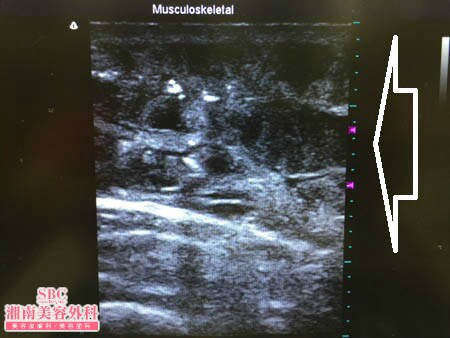

No.177115【脂肪吸引】湘南美容外科脂肪吸引最高責任者である竹田先生によるビフォーアフター!前回の脂肪吸引が大満足だったので今度は二の腕の脂肪吸引を受ける!術中3Dタッチビュー・左二の腕